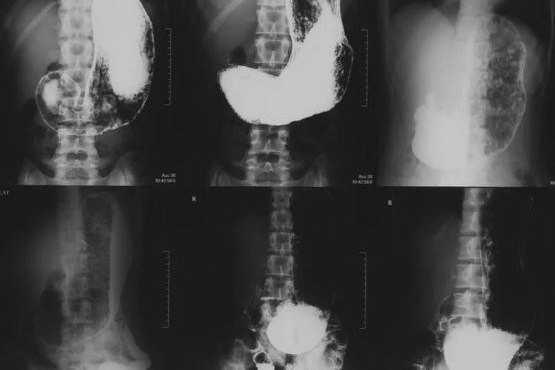

— Рентгеноскопия пищевода, желудка

— Ирригоскопия (исследование толстого кишечника)

ПРАВИЛА ПОДГОТОВКИ К РЕНТГЕНОСКОПИИ ЖЕЛУДКА

Ничего не есть с вечера на кануне исследования минимум за 8 (восемь) часов до исследования.

Последний прием пищи должен быть легким, не содержать жирных, жареных и молочных продуктов.

Воздержаться от курения.